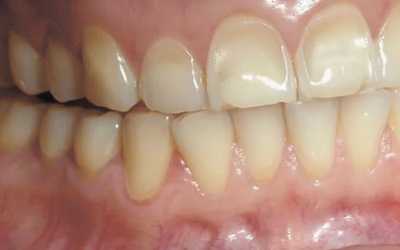

На ортопантомограмме доктор наблюдает полость сферической формы с четко очерченными контурами. На рентген-снимке можно разглядеть корень пораженного зуба с воспаленным периодонтом.